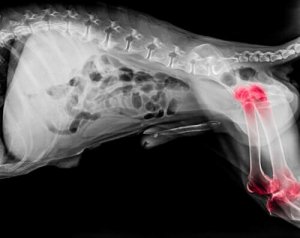

Si ritiene che circa un cane su cinque soffre di artrite. L’artrite è un disturbo articolare che può verificarsi a qualsiasi età, tuttavia i cani più anziani hanno maggiori probabilità di soffrirne. In generale, si può dire che l’artrite è una malattia degenerativa che provoca infiammazione delle articolazioni, sia ai gomiti che alle ginocchia.